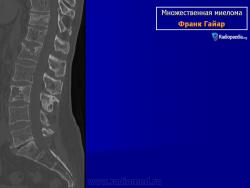

Множественная миелома

Приложения:

slayd1smi.jpgslayd2smi.jpgslayd3smi.jpgslayd4smi.jpgslayd5smi.jpgslayd6smi.jpgslayd7smi.jpgslayd8smi.jpgslayd9smi.jpgslayd10smi.jpgslayd11smi.jpgslayd12smi.jpgslayd13smi.jpgslayd14smi.jpgslayd15smi.jpgslayd16smi.jpgslayd17smi.jpgslayd18smi.jpgslayd19smi.jpgslayd20smi.jpgslayd21smi.jpgslayd22smi.jpg